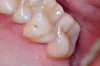

През лятото на 2010 г. - край морето, се запознах с д-р Ивелин Атанасов, той пък ме запозна с Константин Фиалковски и ми направиха проект на ослепителна усмивка - мечта. Цяла година д- р Иво работи тук в Бургас, в „Бо-дент” основно заради мен, съобразявайки се с моите безкрайни ангажименти и пътувания. Той, заедно с д-р Боги Димитров направиха всичко - лекуваха, рязаха, изравняваха по проекта, за да може накрая Fiadenta да ме короняса с уникалните си фасети.

Сега се смея и ми е хубаво, светло и спокойно. Много хора често ме питат какво се е проенило в мен, дали не съм правила пластична операция, ботокс и т.н. А аз се смея!

Обичам си усмивката, обичам хората, които ми я върнаха - д-р Ивелин Атанасов, д-р Богдан Димитров, магьосник Константин Фиалковски и Fiadentа!